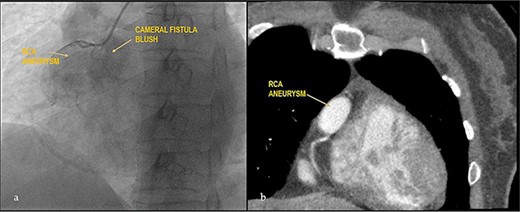

Case 2

Apparently healthy 44-year-female being evaluated as a potential donor for renal transplant, her echocardiography showed dilated right atrium and ventricle with moderate tricuspid regurgitation. Gated cardiac CT was done which revealed proximal RCA aneurysm measuring 2.1×2.4 cm and CAG which revealed RCA–right atrial (RA) cameral fistula. Heart arrested with antegrade cardioplegia after aorto-bicaval cannulation. RA fistula suture ligated through right atriotomy. The aneurysm excised, RCA mobilized and reimplanted into right sinus of valsalva (RSOV). On weaning off of bypass, severe RV dysfunction observed and cardiopulmonary bypass re-initiated. RCA bypass with reverse saphenous vein graft (RSVG) was done. Figures 2 and 3 show radiological and intraoperative images. She had a stormy postoperative course with multiple episodes of ventricular arrhythmias probably attributed to sacrifice of the infundibular and nodal branch, but was eventually discharged on 11th day after surgery.

Giant RCA aneurysm with CCF. (a) CAG showing RCA aneurysm with RA blush; (b) RCA aneurysm in cardiac CT.

CAAn has a reported incidence of 0.3–4.9%, but prevalence of giant coronary aneurysms which are defined when their diameter exceeds >4 times reference vessel or >2cm in adults and >8mm in children is as low as 0.02% [13, 14]. Atherosclerosis in adults and Kawasaki disease in children are the most frequent causes with higher prevalence among females [15]. Right system is most commonly involved (40–70%) and left main stem being rarest (3.5%) [16]. CAAn also shows simultaneous association with cameral fistula in most reported cases usually identified in young population [17]. Their approach is either by aneurysm exclusion with a covered stent or surgical. As our case had ostio-proximal giant aneurysm with cameral fistula, Heart Team Approach decided that surgery would be most appropriate.